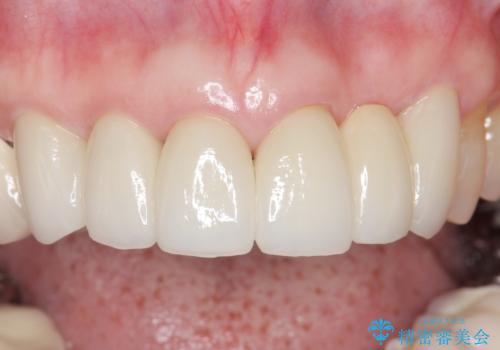

金属を使わないジルコニアセラミッククラウンの自然な仕上がりにご満足頂けました。

被せ物の種類:ジルコニアセラミッククラウン スタンダード